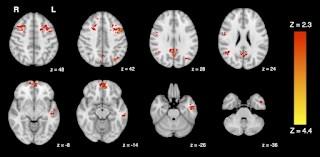

EN SOLO 2 HORAS

Neurociencias. Hasta el 99 % de la población mundial soporta niveles peligrosos de contaminación del aire: se desconoce aún si la exposición crónica puede tener efectos nocivos a largo plazo en el cerebro. Pablo Javier Piacente. Un nuevo estudio concluye que la inhalación de gases de automóviles puede cambiar la conectividad del cerebro en solo 2 horas: los efectos se notaron principalmente en la red de modo predeterminado (DMN), un conjunto de regiones cerebrales interconectadas que están más activas cuando participamos en pensamientos internos, como la introspección y el recuerdo. Investigadores de la Universidad de Columbia Británica y la Universidad de Victoria, ambas en Canadá, han demostrado que los niveles comunes de contaminación del tráfico pueden afectar rápidamente la función del cerebro humano. En solo 120 minutos, la exposición a los gases de escape del diésel provocan una disminución en la conectividad funcional del cerebro, una medida de cómo las diferentes áreas del cerebro interactúan y…leer más